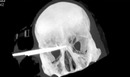

- 奇迹!青年太阳穴被9厘米利刃刺入 侥幸保住视力

- 时间:2013-02-18 09:19:24